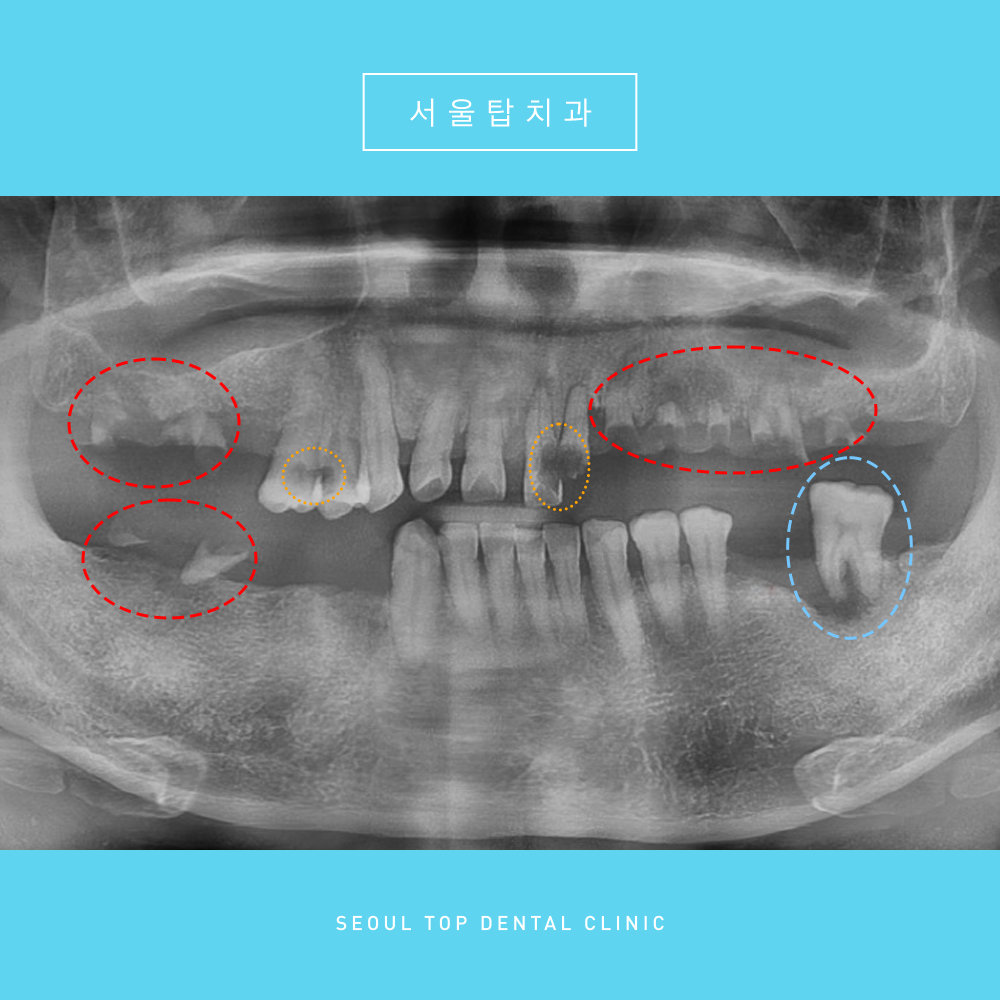

파노라마 사진을 촬영해 체크해보니

전반적인 치아 및 치주 상태가

너무 좋지 않았습니다.

이미 상실된 치아도 다수였으며

어금니 부위는

빨간색 부위의 뿌리만 남아있는 잔존치근과

잇몸뼈가 녹고 뿌리 끝에 염증이 있어

심하게 흔들리는 하늘색 표시의

왼쪽 큰 어금니 하나만 남아있었습니다.

사실상 어금니로 식사가 가능한 부분이 아예 없어

환자분께서는 앞쪽 치아로

식사를 겨우 하고 계신 상황이었습니다.

그리고 뿌리만 남아있는 잔존치근과

흔들리는 왼쪽 아래 어금니 뿐만 아니라

주황색 표시의 충치가 심한

치아들도 확인할 수 있었는데요.

충치가 심하게 진행되어 있고 치주 상태도 좋지 않으며

뿌리 끝 염증이 관찰되는 치아도 있었습니다.

파노라마상 표시해놓은 치아들은

더 이상 살리기 어렵다고 판단하여

모두 발치를 진행하기로 했습니다.